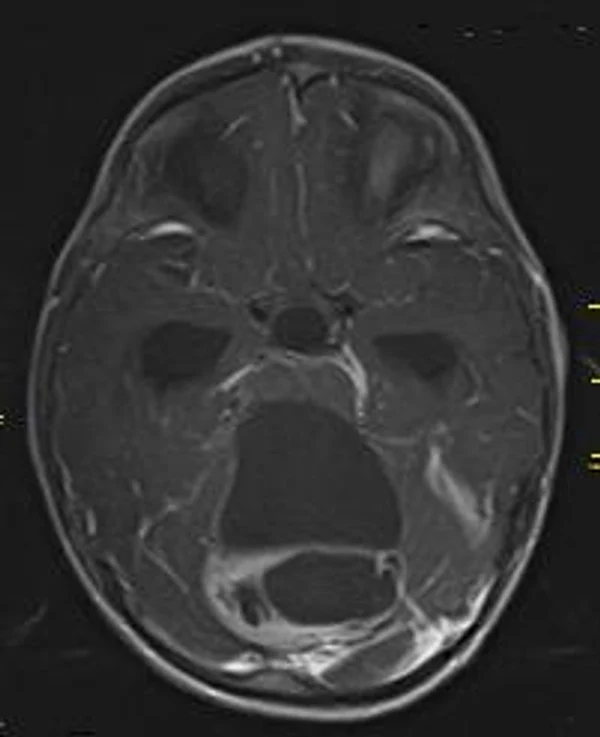

В качестве примера приведены 2 случая хирургического лечения новорожденных с врожденными опухолями головного мозга и позвоночного канала. У новорожденной девочки опухоль (хориодпапиллома) располагалась в области треугольника правого бокового желудочка (рис. 28 а, б). В возрасте 2-х недель жизни опухоль удалена. По данным МРТ головы с внутривенным введением контрастного препарата выполненной через 2 дня после операции опухоль удалена тотально (рис. 28 в). Послеоперационных осложнений не наблюдалось. У второго пациента 2-х нед. жизни врождённая опухоль (нейробластома) располагалась в позвоночном канале на уровне Th10-L3 позвонков (рис. 29 а) и распространялась в забрюшинное пространство. Клиническая картина заболевания складывалась из нижнего вялого парапареза и нарушения функции тазовых органов. Во время операции остистые отростки Th 11-L3 позвонков рассечены по средней линии. Дужки 6 данных позвонков надломлены и разведены в стороны. Опухоль располагалась экстрадурально, отделена от дорзальной поверхности дурального мешка и корешков спинно-мозговых нервов, после чего полностью удалена из позвоночного канала. Половинки дужек позвонков сведены к средней линии и сшиты между собой. Опухолевый узел в забрюшинном пространстве через 2 нед. удален онкологами. Через год после операции по данным МРТ рецидива опухоли нет (рис. 29 б). При спондилографии дефектов задней стенки и деформаций позвоночника не выявлено (рис. 29 в). Мальчик ходит, мочу и кал удерживает.